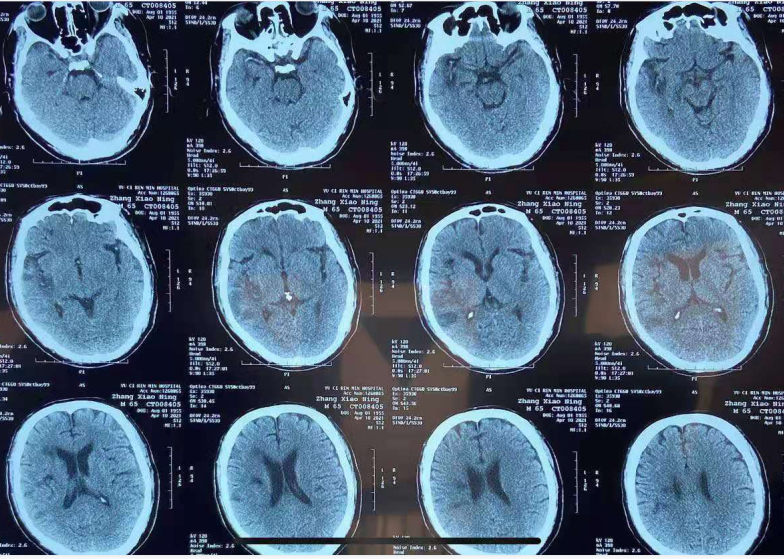

术后影像:

术后8天头颅CT及CTP影像:无出血,右侧半球脑灌注较术前明显改善。